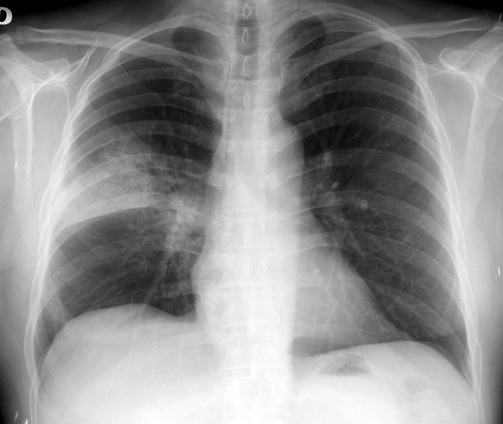

IBP y neumonía adquirida en la comunidad: ¿hay una relación causal?

El uso de los inhibidores de la bomba de protones (IBP) se asocia a un aumento de neumonías en pacientes ambulatorios, pero el riesgo podría explicarse por factores de confusión. BMJ, 15 de noviembre de 2016

Neumonía adquirida en la comunidad: actualización

Boletín INFAC, Información farmacoterapéutica de la Comarca, vol 24 nº 5, 2016